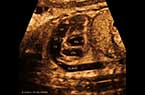

Les plexus choroïdes et le signe du papillon - 12 - 13 SA Les plexus choroïdes et le signe du papillon - 12 - 13 SA Les plexus choroïdes et le signe du papillon - 12 - 13 SA